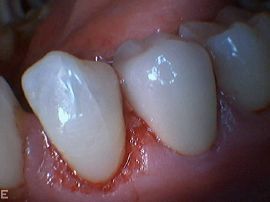

- Kariesbehandlung oder Füllungsersatz durch sorgfältig ausgearbeitete Komposit-Füllungen oder Kronen (amalgamfreie Praxis)

- Metallfreie Keramikkronen und Verblendschalen aus Porzellan (laborgefertigt), vor allem für ästhetisch wichtige Zähne